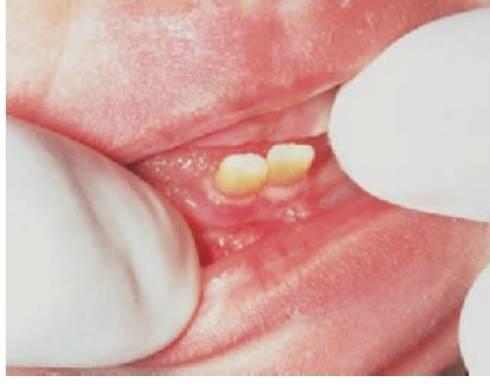

Dientes natales y neonatales

Los dientes neonatales son aquellos que erupcionan en los 30 días posteriores al nacimiento. Los dientes natales estén presentes en el momento del nacimiento y son, en casi todos los casos, incisivos temporales normales que han erupcionado de forma precoz. El desarrollo de estos dientes coincide con la fase esperada de desarrollo de un incisivo temporal en el momento del nacimiento (es decir, sólo se han formado cinco sextas partes de la corona y normalmente no existe raíz). Esta falta de desarrollo de la raíz explica la movilidad de estos dientes. Se debe examinar de forma meticulosa a los lactantes con dientes natales posteriores para descartar otras alteraciones sistémicas que podrían asociarse a otros síndromes y enfermedades (fig. 9.33).

Tratamiento

- El punto más importante que debemos considerar es si la madre puede amamantar de forma adecuada al niño. Si se lesionan los pezones o la superficie ventral de la lengua del lactante, debe extraerse el diente.

- Si los dientes no presentan demasiada movilidad se deben conservar, ya que se reforzarán con el paso del tiempo a medida que la raíz se vaya desarrollando.

- Si los dientes manifiestan una movilidad excesiva, pueden exfoliarse de forma espontánea. No obstante, debido al riesgo teórico de aspiración o ingestión, conviene extraerlos.

- Se debe tener cuidado para extraer el diente entero, ya que con frecuencia se extrae la corona y se deja en el sitio el tejido pulpar. Si esto sucediera, más adelante se formarán la dentina y una raíz que deberá ser extraída transcurrido un tiempo.